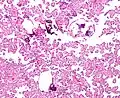

The tumor is neuroectodermal in origin and similar in structure to a normal choroid plexus. They may be created by epithelial cells of the choroid plexus. Papillary fronds lined by bland columnar epithelium are visible under the microscope. Normal absences include mitotic activity, nuclear pleomorphism, and necrosis.[10] Tumors have positive immunohistochemistry for cytokeratin, vimentin, podoplanin, and S-100.[11] Up to 20% of choroid plexus papilloma patients may test positive for glial fibrillary acidic protein (GFAP).[12] Studies have found that fourth ventricle cancers express more S100 than lateral ventricle tumors, and older patients (over 20 years) express more GFAP and transthyretin than younger patients.[13] Some individuals with choroid plexus papilloma have germline TP53 gene mutations, according to genetic analyses.[14] These cancers rarely exhibit nuclear p53 protein positivity. Aicardi syndrome, hypomelanosis of Ito, and 9p duplication are syndromic correlations of choroid plexus papilloma.

Micrograph of a choroid plexus papilloma. H&E stain.

Plexuspapillom Detail

Plexuspapillom Overview